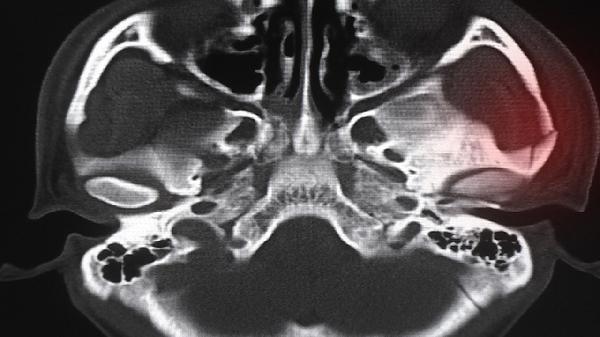

骨折后2-8周骨痂形成期服用健骨生丸可加速愈合,尤其适合老年人髋部骨折或粉碎性骨折患者。此时可能伴随局部肿胀、功能障碍,需定期复查X线评估愈合进度,同时进行康复训练恢复关节活动度。